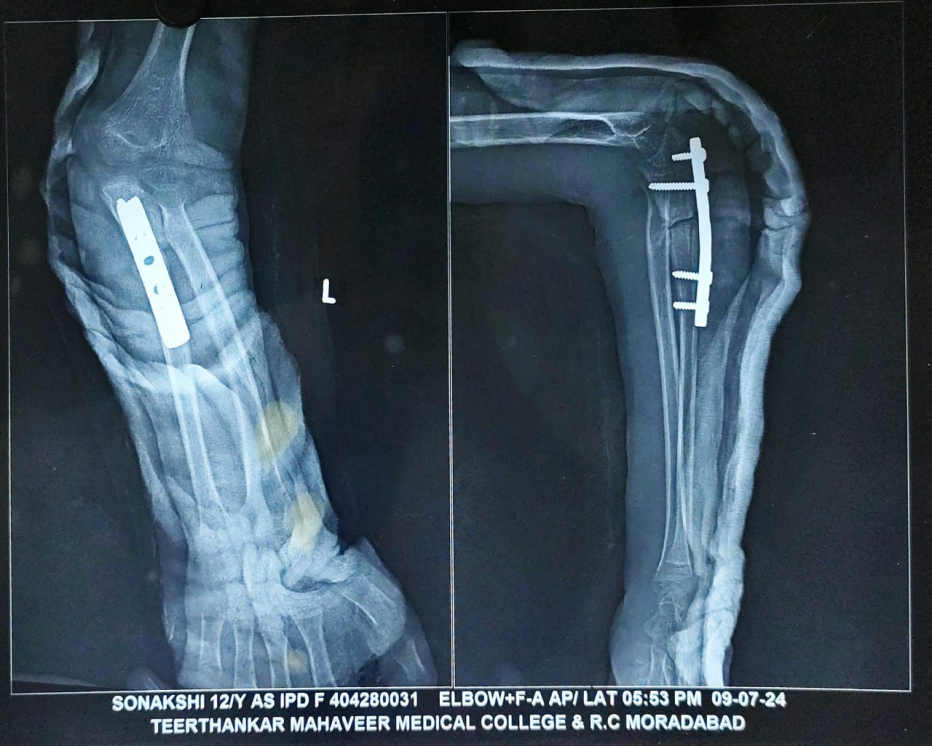

Surgical intervention was planned to restore normal elbow anatomy and function. Under general anesthesia and with tourniquet control, the child underwent open reduction and internal fixation of the ulna with distraction angulation ulnar osteotomy to correct the angulation and length. Across a Boyd approach (Fig. 2), an overcontoured AO 3.5 mm small fragment DCP was used to stabilize the ulnar osteotomy and to ensure proper alignment through which the radial head reduced spontaneously (Fig. 3).

Figure 3: Immediate post-operative X-ray showing reduced radial head with ulnar osteotomy site fixed with AO 3.5 mm small fragment DCP plate.

No open reduction of the radial head was required. Radial head relocation, as well as stability of the radial head, was confirmed intra-operatively. The PIN was not surgically explored in this case, as most nerve injuries associated with Monteggia fractures are neuropraxia and tend to recover spontaneously without the need for intra-operative nerve exploration [8]. In the treatment of Monteggia fractures, plating plays a better role than intramedullary nailing as it provides rigid fixation, allows restoration of ulnar length, and facilitates accurate angulation correction, which is essential for maintaining stable reduction of the radial head [9].